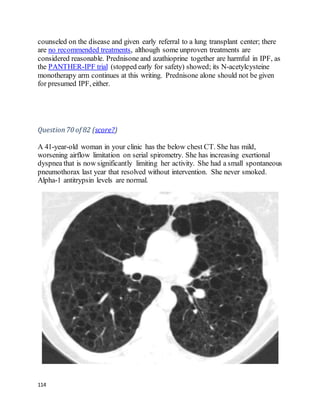

This 49 year old U.S. citizen originally from Trinidad is referred to you for

evaluation by her oncologist. She had the below chest X-ray after a mammogram

suggested abnormal lung parenchyma. Breast biopsy showed ductal carcinoma in

situ. She is to have lumpectomy soon. She has been mildly short of breath since her

20s, which has insidiously gotten worse, although she still works full-time and

takes care of 3 children. She also has a chronic dry cough worse on deep

20

inspiration. She has never sought evaluation for her symptoms and has never had

prior chest imaging. In your office, she walks 1000 feet in 6 minutes, with

desaturation from 100% on ambient air to 85% on ambulation with mild dyspnea.

A TB skin test is placed. An HIV test was negative last year.

PFTs:TLC 70% predicted (below lower limit of normal), FEV1/FVC ratio 0.65,

FEV1 2.1L (below lower limit of normal) DLCO 40% predicted, DLCO/VA 80%

predicted.

We feelthat B is the best answer.

Sarcoidosis is more prevalent in people of African descent, and can present at a

young age and progress insidiously. This woman likely has diffuse lung fibrosis

without hilar lymphadenopathy, so-called stage IV sarcoid. The term "stage"

misleadingly implies a predictable pattern of linear disease progression; in fact, the

radiographic pattern (stage) correlates neither with chronicity nor with changes in

pulmonary function.

Miliary TB would be expected to producea more nodular pattern on chest films, as

opposedto this linear or reticular pattern. In situ cancer would not likely have

spread lymphangitically. IPF usually preferentially affects the peripheral and basal

lungs. The small nodule in the right lung baseis probably of no significance.